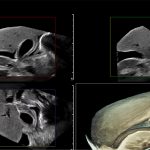

Imagini clinice:

Aplicatii: